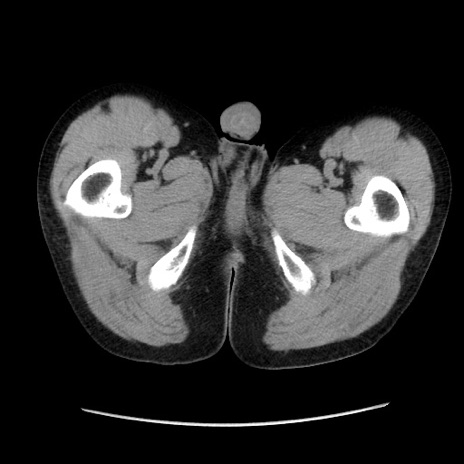

症例37(横断像)

【症例】40歳代 男性

【主訴】腹痛

【現病歴】4時間ほど前に電車に乗車中に臍部上より腹痛出現。徐々に増悪し起立困難となり、救急外来受診。生ものは数日食べていない。今朝お雑煮を食べた。

【身体所見】BT 36.8℃、BP 117/84mmHg、HR 91/min、SpO2 97%、苦悶様、腹部:臍上部広範囲圧痛あり、反跳痛±

【データ】WBC 8100、CRP 0.03